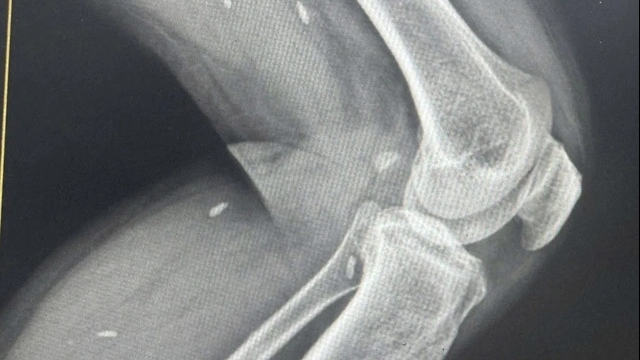

Cùng với đó là hệ thống trang thiết bị hiện đại, dẫn đầu y học thế giới như: Máy chụp cộng hưởng từ (MRI) 1.5 Tesla của hãng GE Hoa Kỳ, máy chụp cắt lớp vi tính (CT Scanner) đa dãy, hệ thống siêu âm màu 5D, cùng dàn máy xét nghiệm tự động đạt chuẩn quốc tế.

Đặc biệt, đơn vị có công nghệ trí tuệ nhân tạo (AI) được tích hợp trong chẩn đoán hình ảnh, giúp phát hiện sớm và chính xác nhiều bệnh lý phức tạp cũng như các tổn thương siêu nhỏ khác. Hệ thống phòng mổ vô khuẩn một chiều cùng thiết bị nội soi hiện đại cho phép thực hiện các ca phẫu thuật ít xâm lấn, giảm đau đớn và rút ngắn thời gian hồi phục cho bệnh nhân.